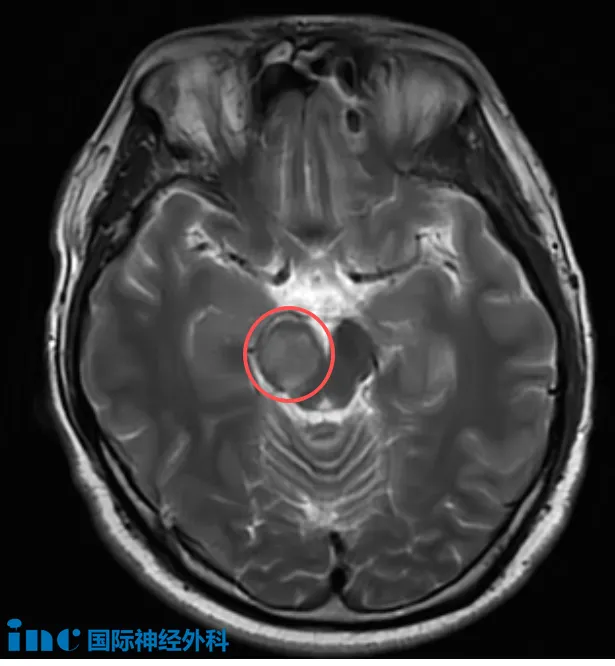

31歲的吳先生,正處于人生與事業(yè)的黃金階段,卻在2025年8月下旬因一次突如其來的頭暈與耳悶,查出右側中腦存在病變,自此與位于“生命中樞”的未知病變展開了較量。當?shù)蒯t(yī)院懷疑腫瘤可能性大,隨后其癥狀在9月初消失,醫(yī)生又建議觀察。為尋求明確答案,一家人又奔赴北京,得到的回復是“考慮腦干膠質(zhì)瘤,可以手術治療”。

“這并不是一個容易的手術,如果用1到10來衡量難度,我會給它大約7分。它不是最困難的手術,但確實比一般手術要復雜和苛求得多。關鍵在于,在盡量實現(xiàn)廣泛切除的同時,保持患者的運動和感覺功能,實現(xiàn)切除與保護之間的平衡。這確實不容易,但我已在過去40多年中不斷學習和實踐,正是為了掌握如何做到這一點。我已經(jīng)成功完成了非常多類似的手術,也正因為如此,我對這臺手術充滿信心!”這是巴教授深耕腦干多年的自信。

影像